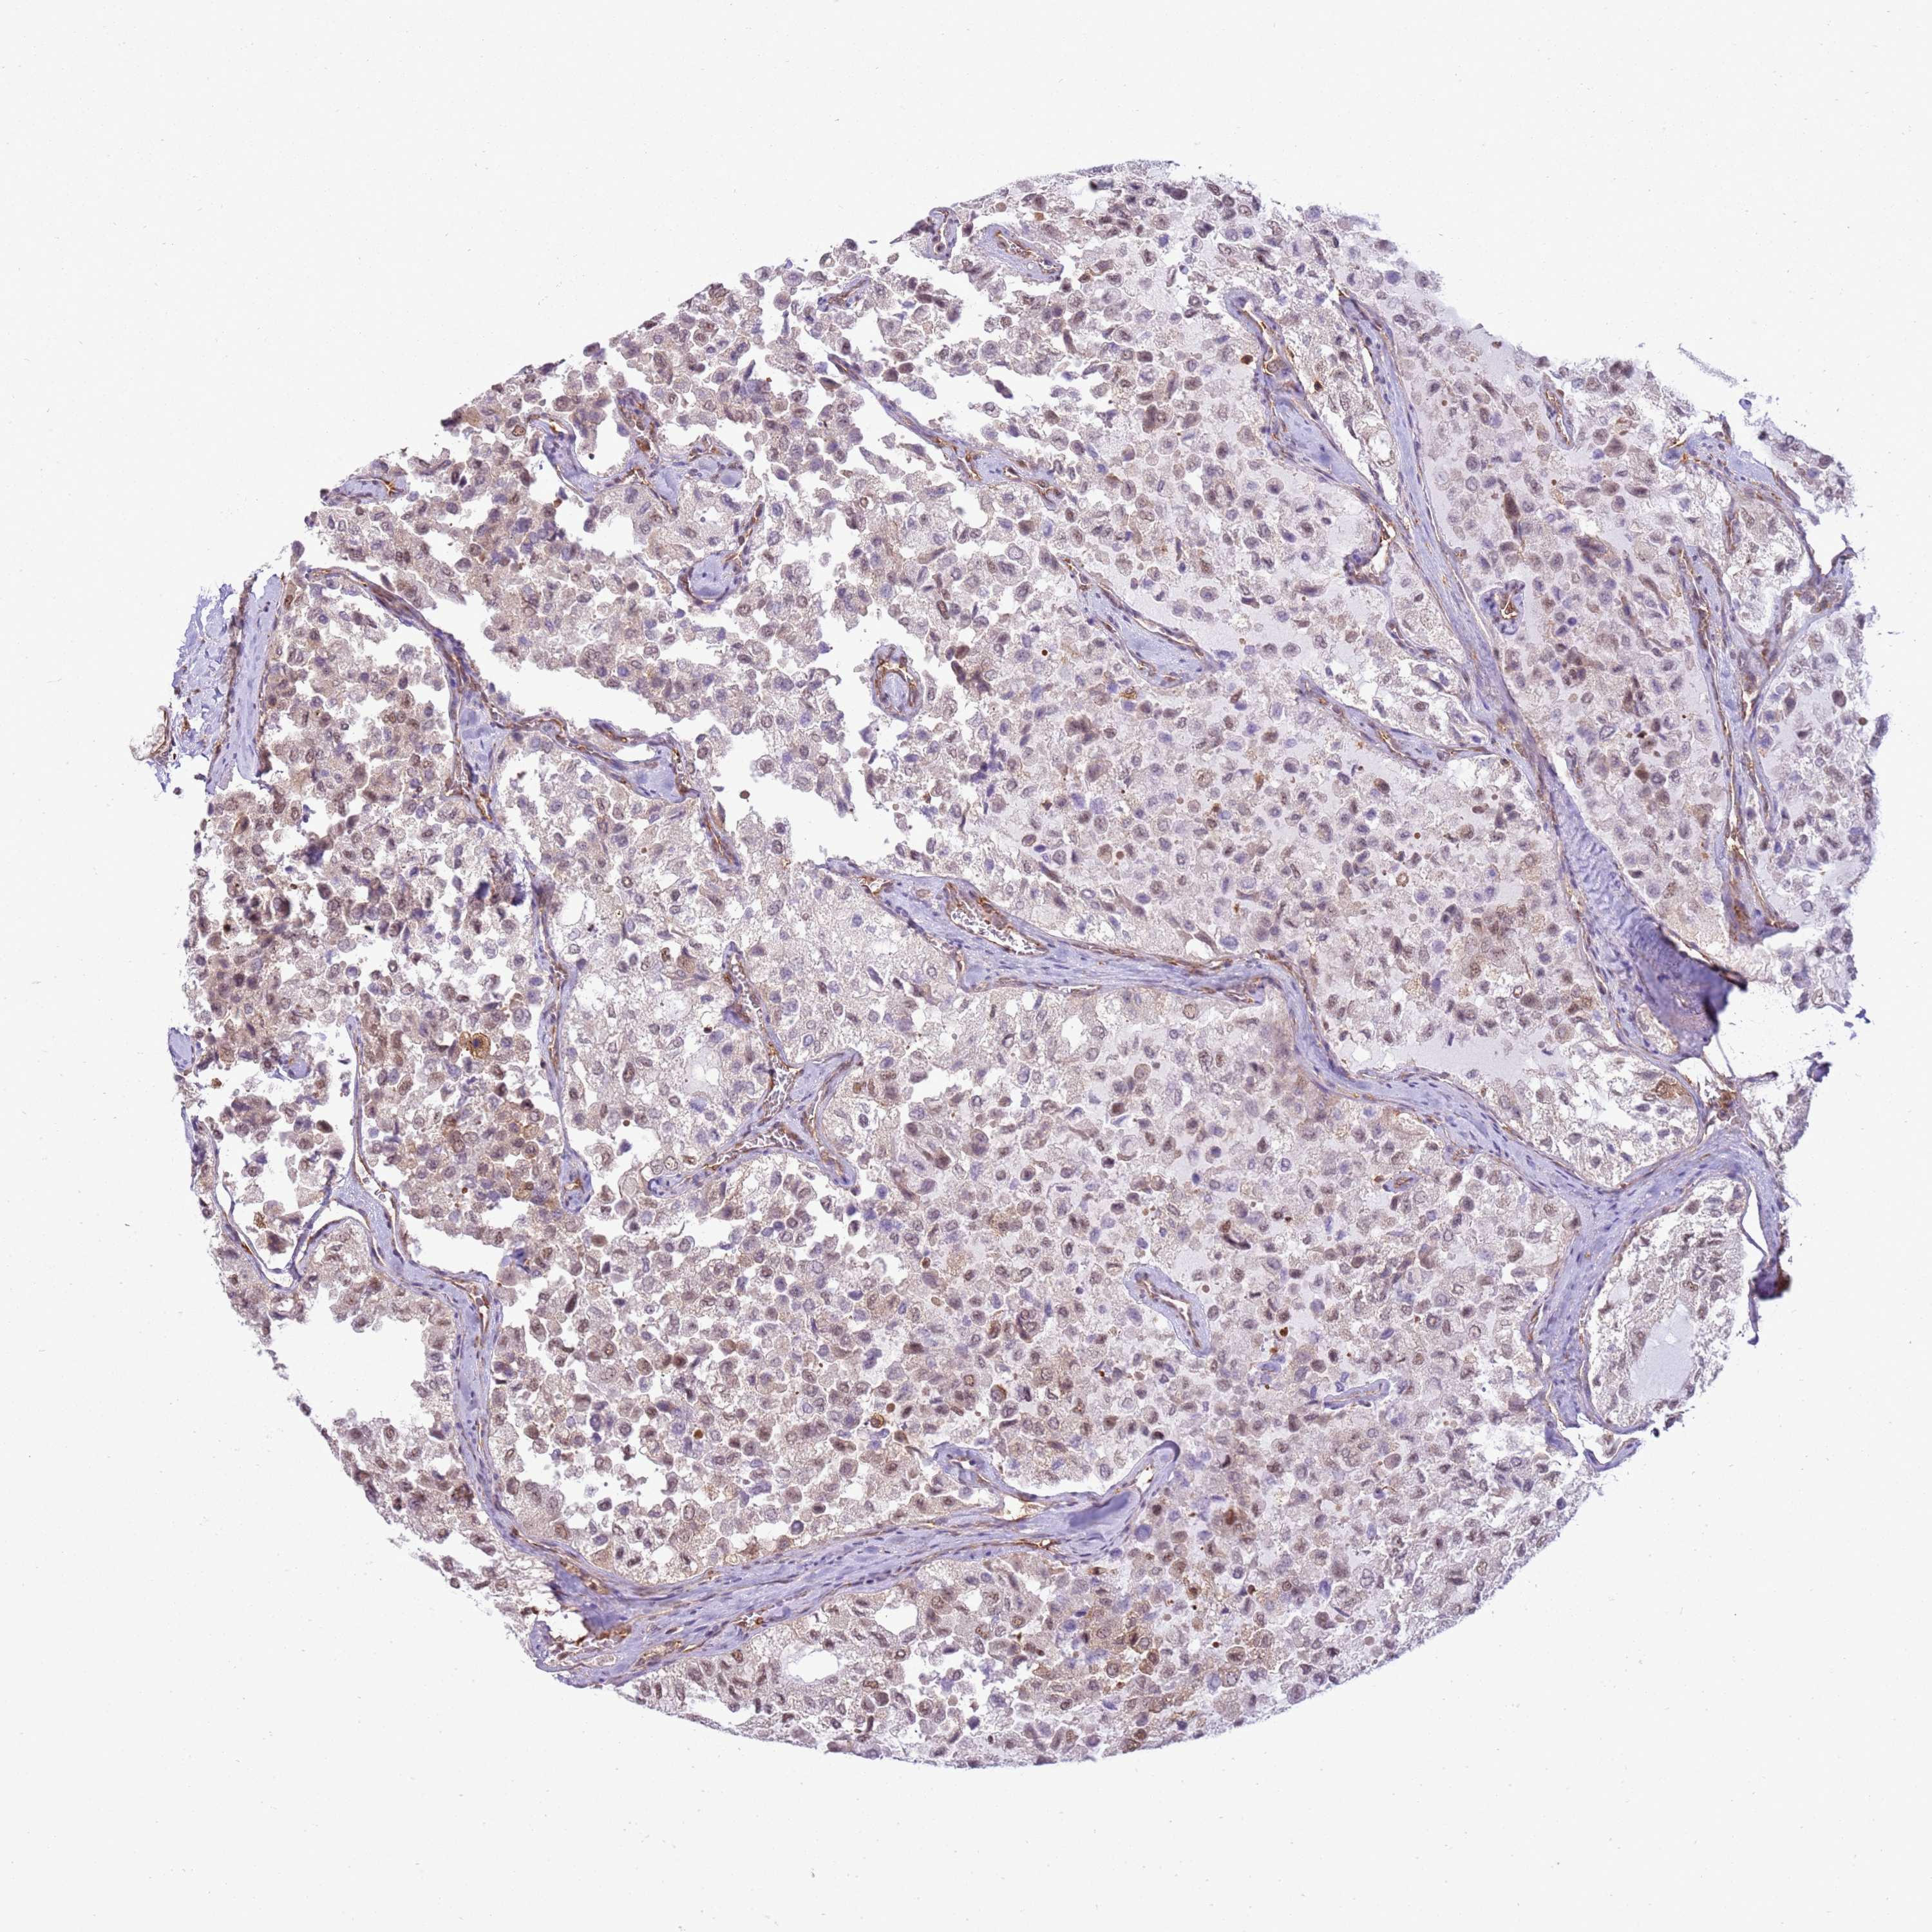

THYROID CANCER - Protein expressioni

A mouse-over function shows sample information and annotation data. Click on an image to view it in a full screen mode. Samples can be filtered based on level of antibody staining by selecting one or several of the following categories: high, medium, low and not detected. The assay and annotation is described here.

Note that samples used for immunohistochemistry by the Human Protein Atlas do not correspond to samples in the TCGA dataset.

Antibody stainingi

Antibody staining in the annotated cell types in the current human tissue is reported as not detected, low, medium, or high, based on conventional immunohistochemistry profiling in selected tissues. This score is based on the combination of the staining intensity and fraction of stained cells.

Each image is clickable and will lead to virtual microscopy that enables deeper exploration of all samples and also displays staining intensity scores, fraction scores and subcellular localization as well as patient and tissue information for each sample.

Antibody HPA045918

Staining

High

Medium

Low

Not detected

Intensity

Strong

Moderate

Weak

Negative

Quantity

>75%

75%-25%

<25%

None

Location

Nuclear

Cytoplasmic/membranous

Cytoplasmic/membranous,nuclear

Papillary adenocarcinoma, NOS

Follicular adenoma carcinoma, NOS